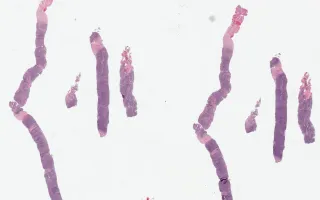

Histologically, the lymph nodes are characterized by collagen bands that surround at least one nodule, and scattered Hodgkin and Reed-Sternberg (HRS) cells with lacunar morphology. Eosinophils, histiocytes and to a lesser extent neutrophils are often numerous.

This slide shows H&E stain. See Related Content for CD30, CD15, PAX5, and MUM1.